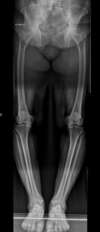

La plupart des gens souffrant d’arthrose du genou ont un tibia arqué (genu varum en langage médical). C’est pourquoi souvent l’arthrose débute dans la zone en dedans du genou (compartiment interne ou médial)

arthrose du genou, compartiment médial, sur déformation en genu varum

Arthrose médiale des 2 genoux avec grande déformation en varus